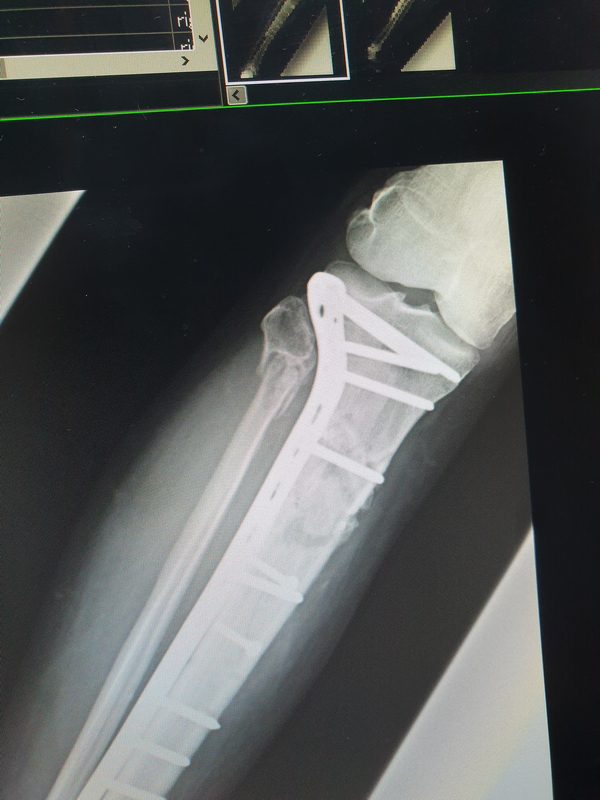

It was with some confidence that I went for a check up & xrays at the hospital to determine my broken legs bones having knitted well & ready for a full 100% load after 3.5 months.

1665913260172.png

Disappointed I was & we still have a way to go.

Must be something to with age I guess.

1665913323436.png

It will be a while longer before I'm back on the Vstrom